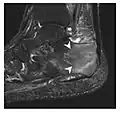

Fatigue fractures are more frequent in women which may be due to the relatively smaller bones of women. Moreover, pregnancy is a well-recognized risk factor for femoral neck fatigue fracture. While fibular and metatarsal fractures have a low risk of complications, other sites including the femoral neck, midanterior tibia, navicular, talar, and other intraarticular fractures are prone to complications such as delayed union, nonunion, and displacement. The site of the insufficiency fracture may be specific to the activity: for example, rugby and basketball players are more prone to navicular fractures, while gymnasts have a higher risk for talar fractures (Figure 7). Long distance runners are at increased risk for pelvic, tibial (Figures 8 and 9), and fibular fractures. In the military, calcaneus (Figure 10) and metatarsals are the most commonly cited injuries, especially in new recruits. Billiard players are at risk for upper limb fractures (Figure 11).[1]

Figure 7: Fatigue fracture of the talus in a 25-year-old male basketball player with right hind foot and ankle pain, without history of trauma, and a normal initial radiograph (not shown). (a) One-month followup lateral radiograph shows normal appearance. (b) Sagittal T1-weighted MRI shows an irregular fracture line (arrow) within an ill-defined area of hypointensity corresponding to bone marrow edema.[1]